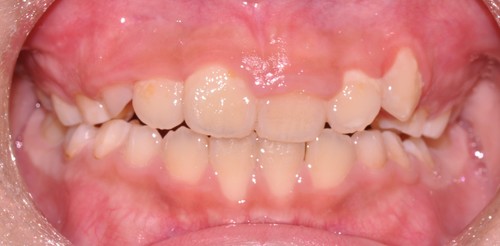

前歯が全体的に受け口になっている症例はもちろんですが、下の写真のように1本だけ反対になっている症例にも効果があります。

↓

4カ月で左前歯の反対咬合が改善されています。さらに歯列の拡大も見られます。